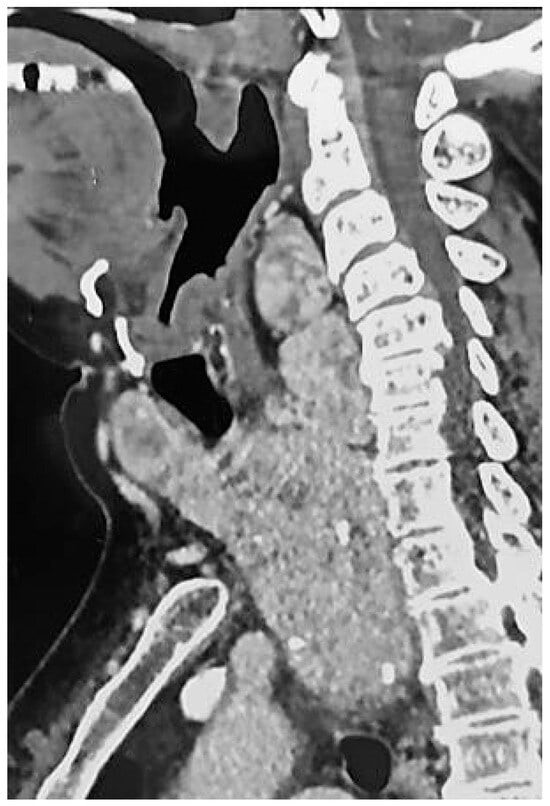

体格检查显示患者身高149厘米,体重84公斤,BMI为37.8 kg/m2(归类为肥胖:BMI ≥ 30)。她的颈周测量为49厘米,位于颈椎中部与前颈部之间。上呼吸道检查显示Mallampati评分为4,临床上明显有大型甲状腺肿,未观察到颅面异常。检查时甲状腺下缘无法触及。然而,颈部和胸腔的计算机断层扫描(CT)确认甲状腺多节增大,伴有咽后部扩张、胸骨下肿大和气管压迫,且无显著脱位。呼吸障碍监测显示严重阻塞性呼吸暂停(OSA),AHI为每小时32次事件(归类为严重OSA:AHI≥30),主要表现为阻塞性低通气。

术前呼吸管理后,患者接受了新的耳鼻喉科上呼吸道内镜检查,显示擧绳类压迫伴有水肿,且两声带活动正常。随后,在突尼斯拉拉布塔大学医院耳鼻喉科进行了全身麻醉下的全甲状腺切除术。术后,患者报告了声音质量的轻微变化。对切除甲状腺的宏观检查显示尺寸增大,右叶7×5 × 3厘米,左叶12 × 7 × 5厘米,地峡3×2厘米。组织学分析确认无恶性肿瘤。患者接受了左甲状腺素替代疗法,剂量为125微克/天。